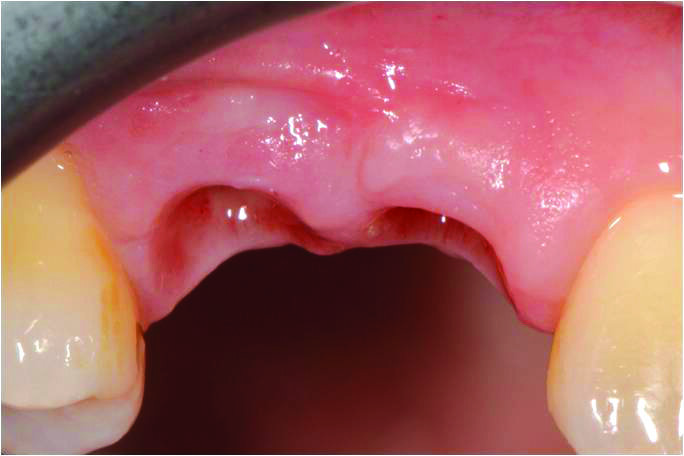

Dopo una fase di maturazione di 3 mesi è stato osservato un significativo aumento sia dello spessore che dell’altezza della mucosa cheratinizzata perimplantare. La maturazione dei tessuti evidenzia come l’inserzione del frenulo vestibolare sia migrata apicalmente rispetto alla sua posizione originale (Figg. 9, 10).

Figg. 9, 10_Dopo una fase di maturazione di 3 mesi, è stato osservato un significativo aumento del volume dei tessuti molli buccali e un miglioramento del deficit verticale dei tessuti molli.